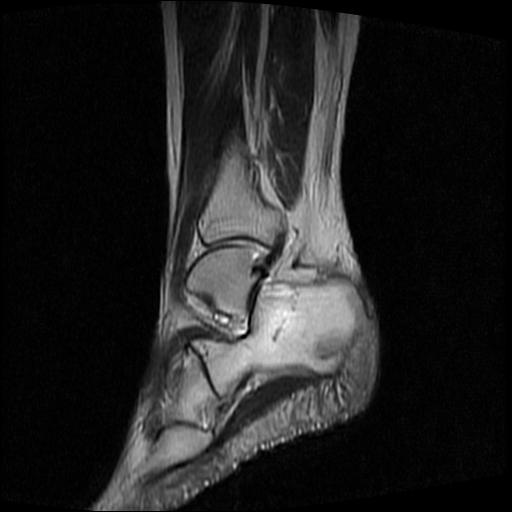

女性,70岁,右侧跟骨疼痛2个月,负重时加剧,不负重时不疼。

胫骨下段,跟骨、距骨可见斑片状异常信号区;考虑:转移瘤

跟骨长t1长t2信号异常,边缘模糊(肿瘤一般边界清楚,故肿瘤不考虑),压脂像呈高信号--骨髓水肿(炎症?)。